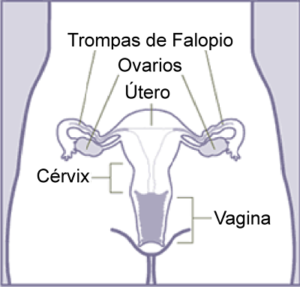

Anatomía

Vagina

La vagina forma parte de los genitales internos de la mujer. En la parte superior de la misma se encuentra el cuello uterino; la parte inferior es la apertura al exterior.

Vulva

Se conoce como vulva al conjunto de órganos genitales externos de la mujer. Está conformada por los labios mayores y menores, el clítoris y el monte del pubis o monte de Venus.